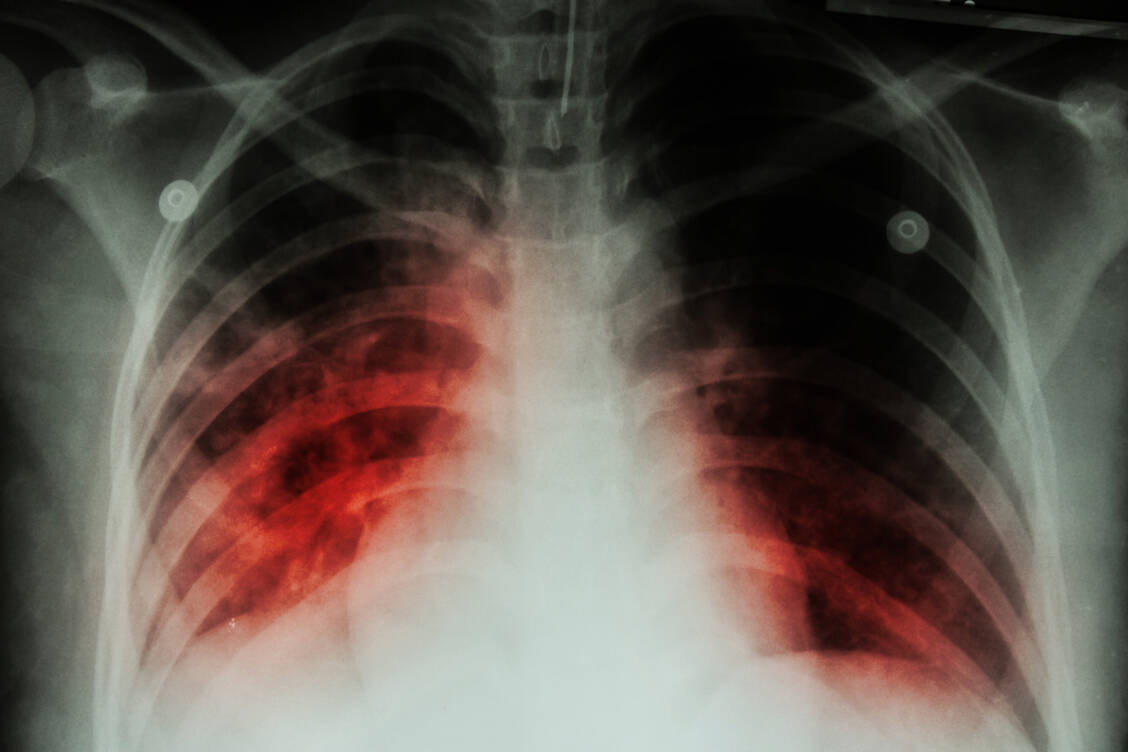

Tuberkulose

Jeder fünfte Fall in Europa bleibt unerkannt

Unentdeckte Tuberkulose-Fälle, Ausbreitung resistenter Erreger – beides hängt Experten zufolge zusammen und gefährdet den Kampf gegen die Krankheit. Hinzu kommt eine gewaltige Finanzierungslücke.

Tuberkulose wird unter anderem über die Luft übertragen. Zu den Symptomen zählt vor allem Husten, möglich sind zudem Brustschmerzen und Appetitverlust. Die Bakterien können neben der Lunge auch andere Organe befallen. Ohne Behandlung führt eine Tuberkulose-Erkrankung laut WHO-Daten bei etwa jedem zweiten Betroffenen zum Tod.